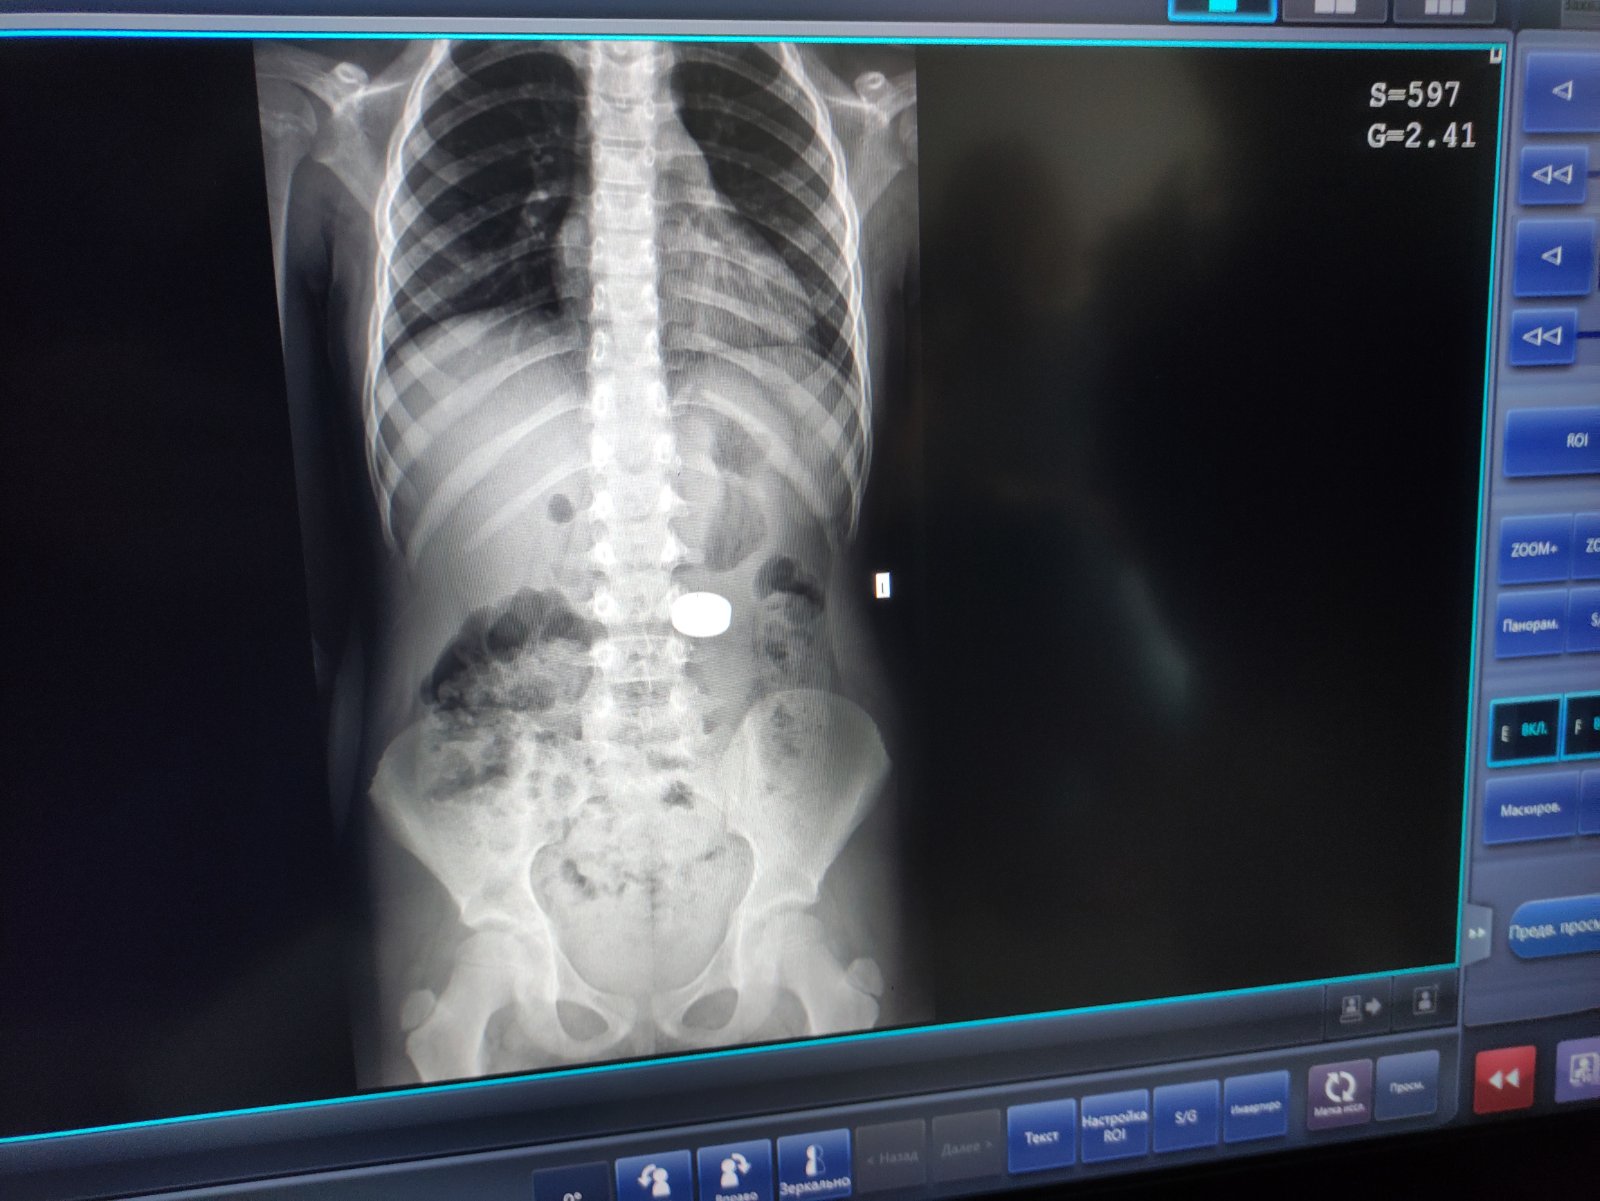

"Магніти були великого діаметра. Під їхньою вагою шлунок опустився до рівня тазових кісток. Тому спочатку візуально вони локалізувались у кишківнику. Проте ми провели пацієнтці додаткове рентгендослідження у лежачому положенні, і зрозуміли, що сторонні тіла ще у шлунку, тож можна видалити їх ендоскопічно", - додав фахівець.